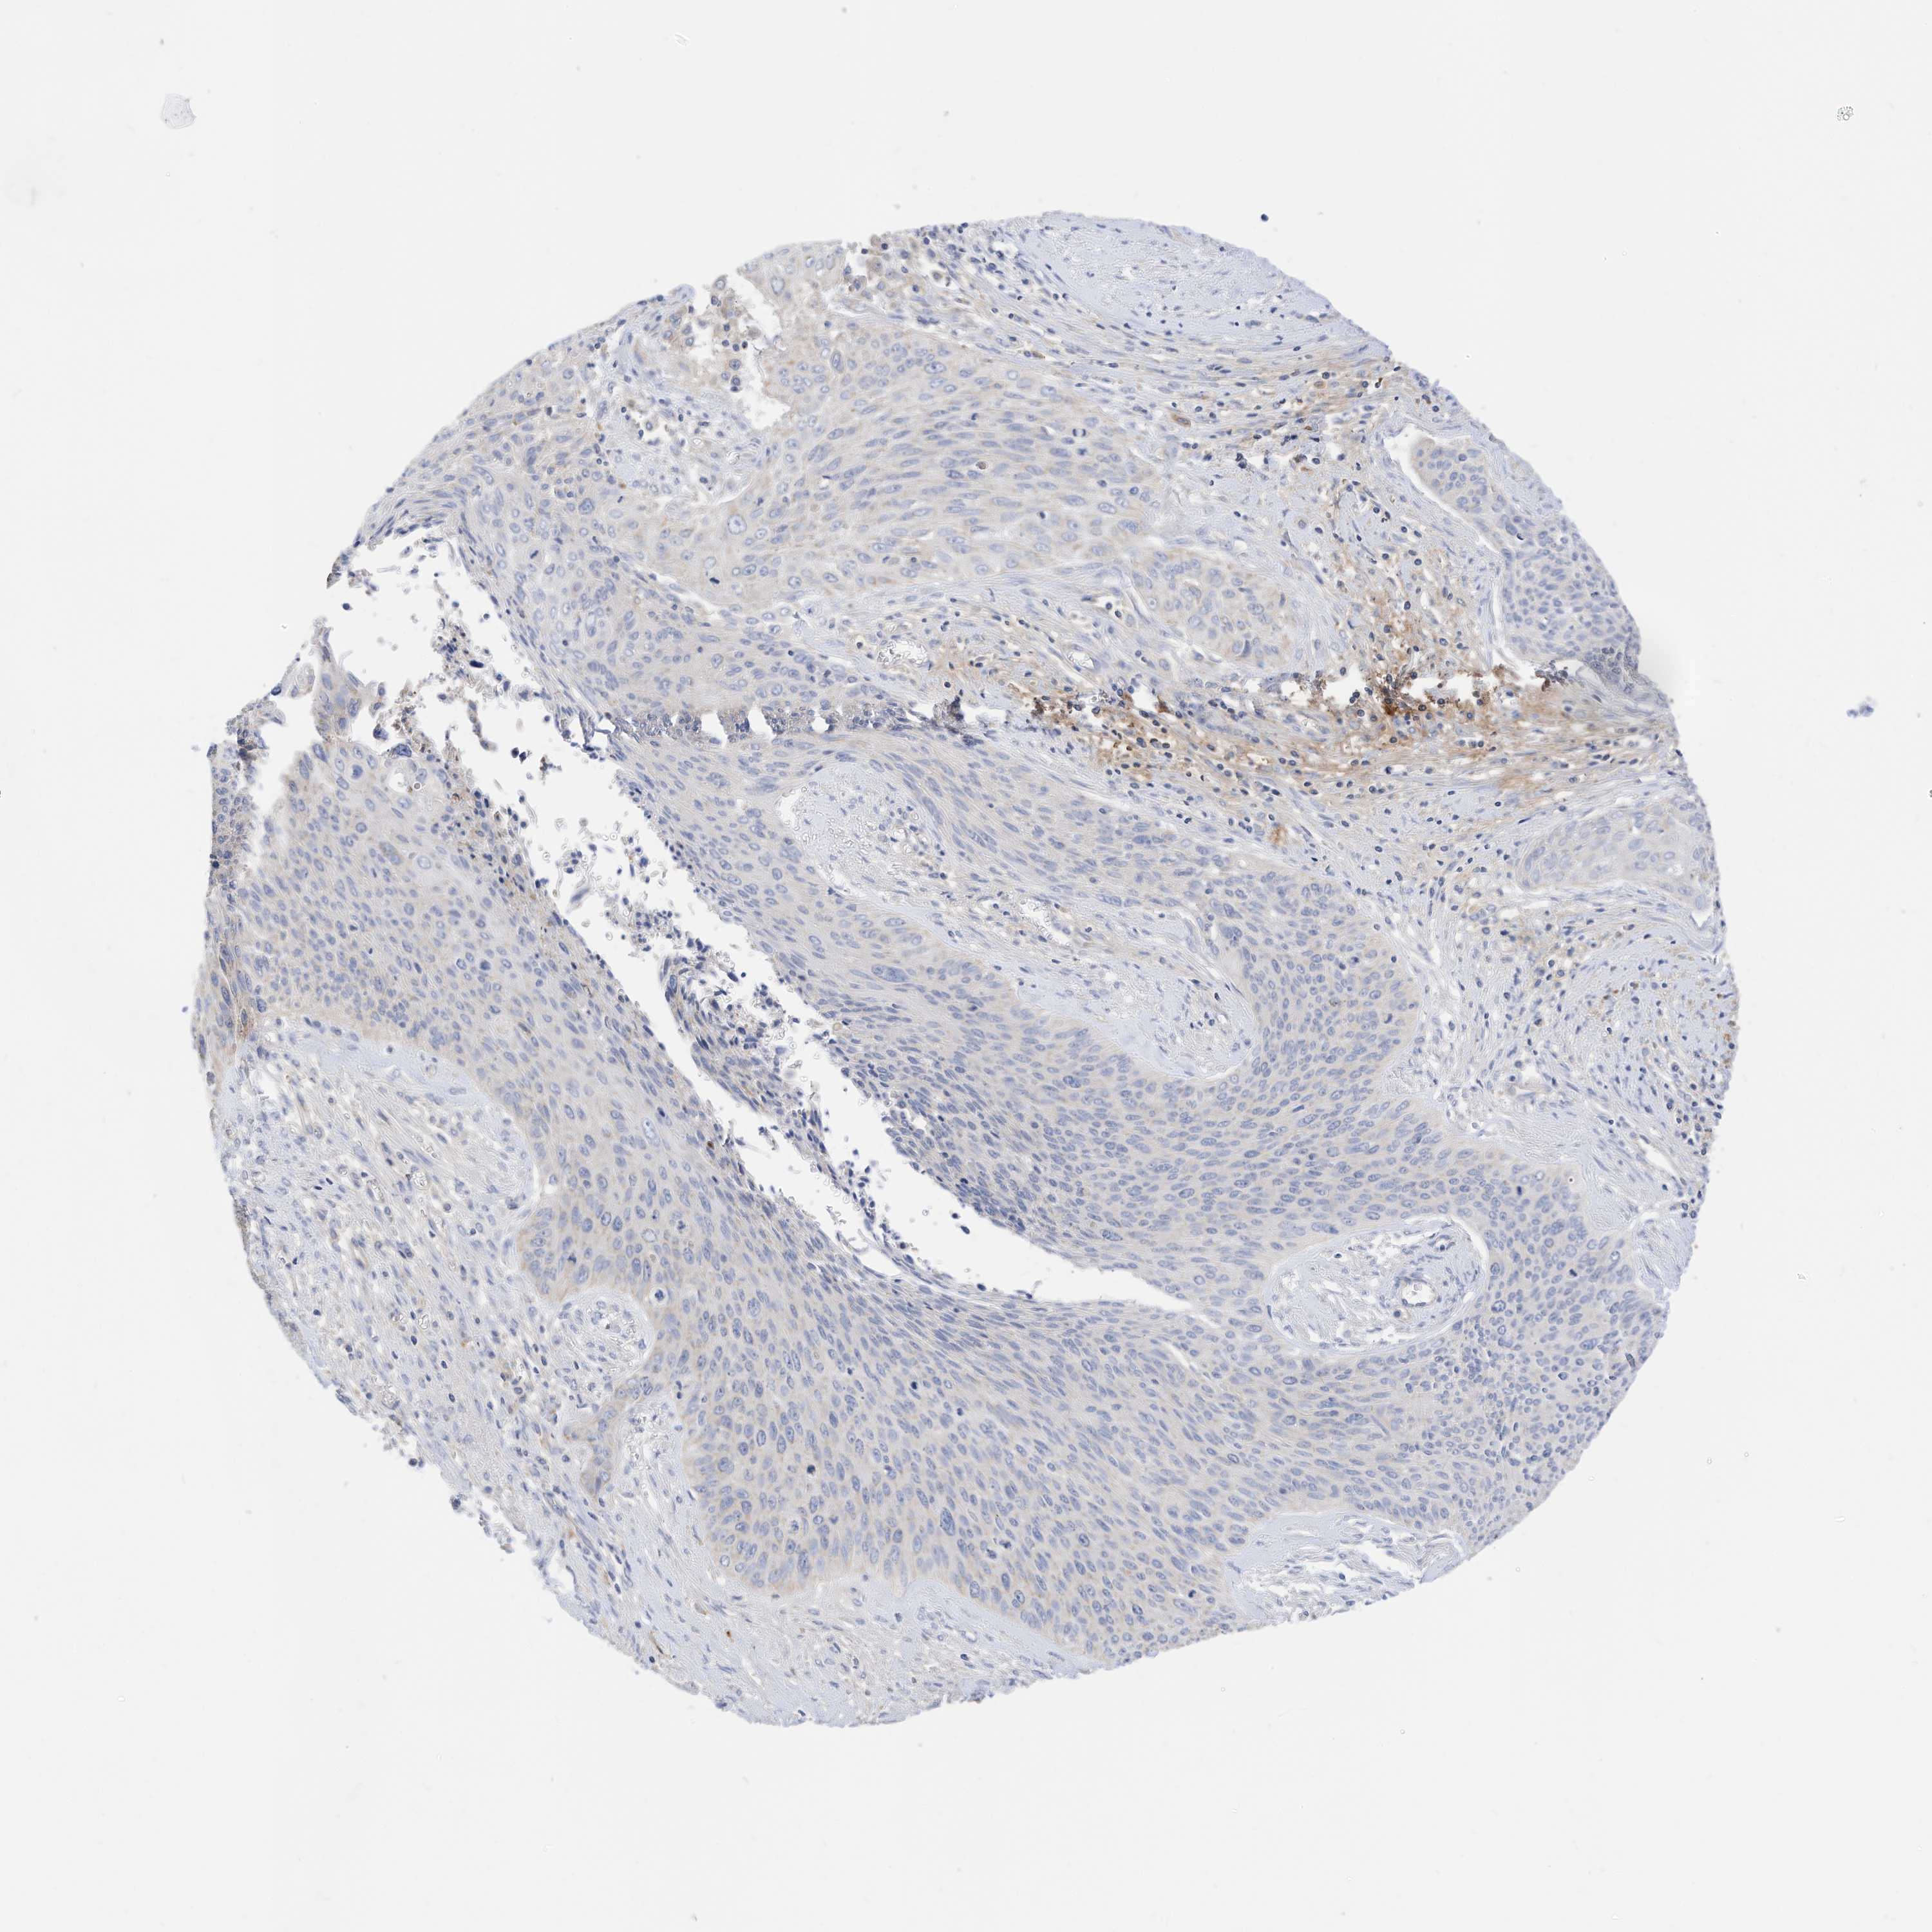

CERVICAL CANCER - Protein expressioni

A mouse-over function shows sample information and annotation data. Click on an image to view it in a full screen mode. Samples can be filtered based on level of antibody staining by selecting one or several of the following categories: high, medium, low and not detected. The assay and annotation is described here.

Note that samples used for immunohistochemistry by the Human Protein Atlas do not correspond to samples in the TCGA dataset.

Antibody stainingi

Antibody staining in the annotated cell types in the current human tissue is reported as not detected, low, medium, or high, based on conventional immunohistochemistry profiling in selected tissues. This score is based on the combination of the staining intensity and fraction of stained cells.

Each image is clickable and will lead to virtual microscopy that enables deeper exploration of all samples and also displays staining intensity scores, fraction scores and subcellular localization as well as patient and tissue information for each sample.

Antibody HPA030345

Staining

High

Medium

Low

Not detected

Intensity

Strong

Moderate

Weak

Negative

Quantity

>75%

75%-25%

<25%

None

Location

Nuclear

Cytoplasmic/membranous

Cytoplasmic/membranous,nuclear

Squamous cell carcinoma, NOS

Adenocarcinoma, NOS